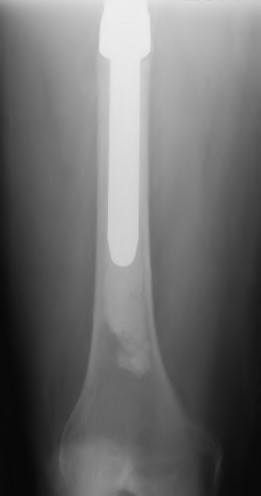

According to the classification of cementless femoral stems, a fully porous-coated cylindrical stem relies on which area for its primary mechanical fixation?

Explanation

In revision total hip arthroplasty (THA), an Extended Trochanteric Osteotomy (ETO) is often planned to remove a well-fixed cementless stem. To ensure successful extraction and subsequent stable fixation of a fully porous-coated cylindrical revision stem, what is the biomechanical principle regarding the length of the ETO fragment?

A patient requires a femoral revision THA for aseptic loosening. Radiographs demonstrate extensive metaphyseal bone loss with the diaphyseal cortical bone remaining fully intact for only 3 cm distal to the tip of the current stem. According to the Paprosky femoral defect classification, what type of defect is present?